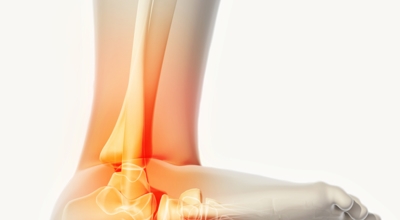

족저 근막이란 발가락 시작지점부터 발뒤꿈치뼈까지 발바닥 전체를 감싸고 있는 두꺼운 막을 말해요. 족저 근막은 발바닥 아치를 보존시켜 발바닥이 지면을 내딛음으로써 생기는 쇼크을 흡수하는 중요시되는 역할을 수행하고 있어요. 이 족저 근막에 일차적으로 서서히 조직 훼손이 일어나고 계속적인 활동에 의하여 염증이 커지면서 발 뒤꿈치 부근 통증을 일으키게 되는데 염증은 무리하고 반복적인 동작, 많은 활용으로 마찰에 의해 발생해요.

족저 근막염은 염증에 의한 훼손 및 통증을 유발하는 질환인데요 족저 근막염 증상은 동일한 발뒤꿈치 통증 하글런드 병변의 기형으로 알려져 있으고 아킬레스 건과 연관이 깊다고 해요. 특히 근육이 덜 풀린 아침 시간 대는 보행 시 날카롭고 바늘로 찌르는 듯한 심한 통증을 느끼게 된다고 해요. 하지만 아침 시간 대를 지나 오후에 접어들면서 일정 양 통증은 서서히 감소하기 시작한다고 하는데요 초기 증상이 나타난다면 필수로 전문의를 찾아 조기치료하는 것이 바람직해요.